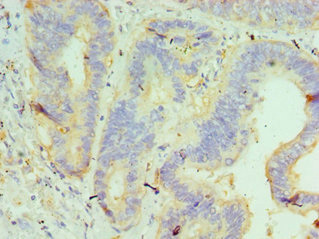

Immunohistochemistry of paraffin-embedded human colon cancer using CSB-PA010064ESR1HU at dilution of 1:100